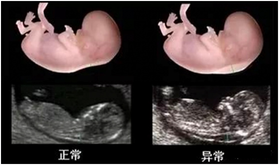

NT檢查(11~13+6周內(nèi))

1、胎兒染色體異常篩查(14-20周)

2、胎兒系統(tǒng)超聲檢查(四維大排畸:22-26周)

除了常規(guī)檢查以外,尚需要進(jìn)行系統(tǒng)全面的胎兒超聲檢查,俗稱“大排畸”,以全面了解胎兒的生長發(fā)育情況。